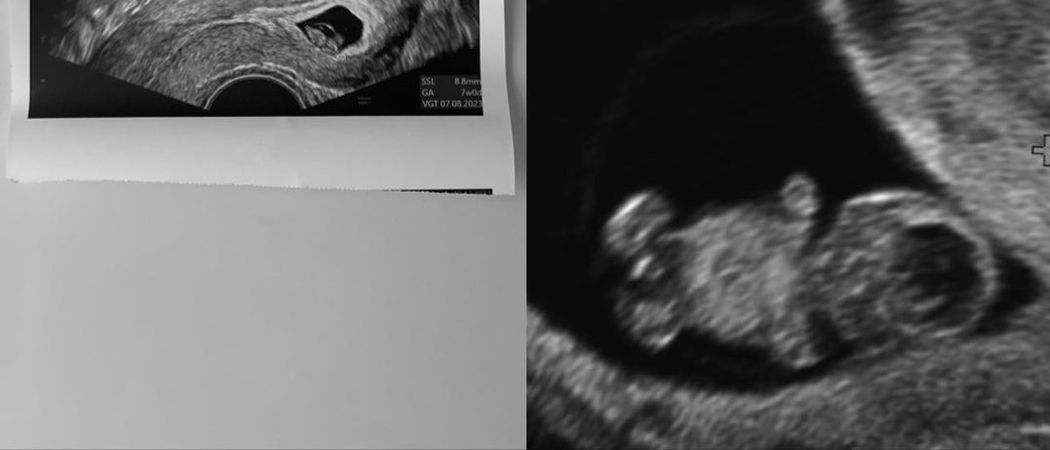

In ihrer Instagram-Story teilte die werdende Mama ein paar kleine Infos rund um ihr Kind: Anna ist derzeit in der zwölften Woche und ihr Baby ist bereits 5,4 Zentimeter groß und wiegt rund 14 Gramm! Außerdem zeigte das Model noch ein Ultraschallbild und verglich es mit früheren Aufnahmen. Und tatsächlich: Es ist schon deutlich ein Baby zu erkennen!